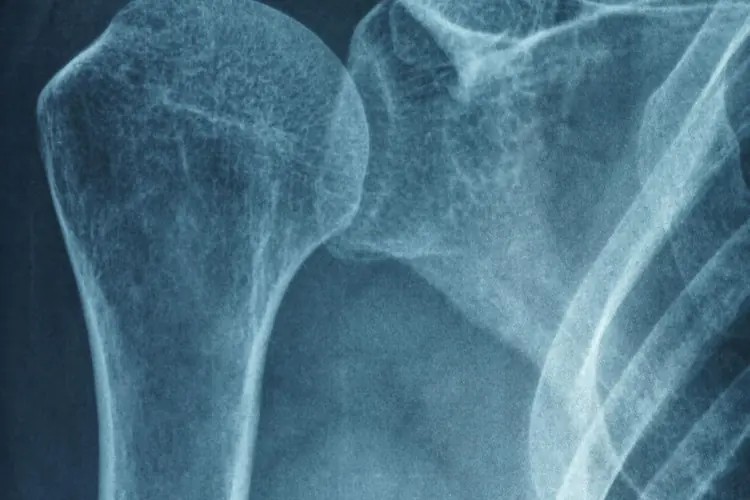

Artrosi

Cos'è l'Artrosi: L'artrosi, conosciuta anche come osteoartrosi o osteoartrite, è una condizione medica cronica che colpisce le articolazioni. È la forma più comune di artrite ed è caratterizzata dall'usura e dalla degenerazione della cartilagine articolare, il tessuto che riveste le estremità delle ossa nelle articolazioni. L'artrosi può colpire qualsiasi articolazione del corpo, ma è più frequente in quelle che sono più soggette a stress e movimenti ripetitivi, come le articolazioni delle mani, delle ginocchia, delle anche e della colonna vertebrale.